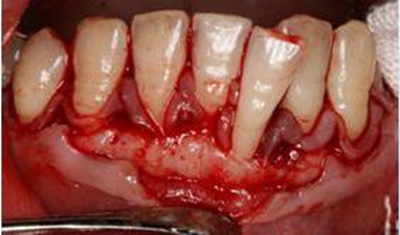

2。牙周手術(shù)治療:

當(dāng)牙周袋較深時,在基礎(chǔ)治療完成6~8周后,如果還存在5mm以上的牙周袋,探診出血,或者存在牙槽骨形態(tài)不良等,需進行一系列牙周手術(shù)以進一步徹底的清除牙周袋內(nèi)的感染物質(zhì)、恢復(fù)牙槽骨及牙齦的正常形態(tài)。

5.jpg

按病情不同需要做不同手術(shù),如牙周翻瓣術(shù)、引導(dǎo)骨組織再生術(shù)、膜齦手術(shù)等。